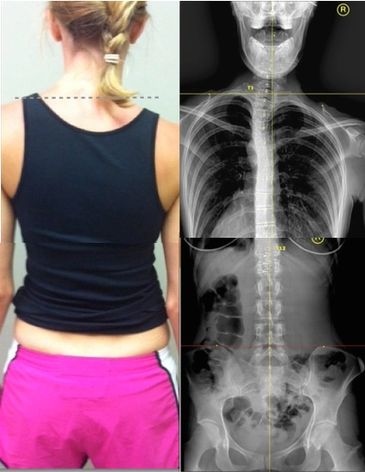

We begin by looking closely at your posture. This may include photos, leg checks, or X-rays. These simple observations give us the clues we need.

Your body balances around three key bones — one in your head (sphenoid), one in your neck (C5), and one in your lower back (L3). We check how these are lined up with gravity.

The body follows predictable patterns when it’s out of balance. We identify which of the eight “balance codes” your body is using to compensate.